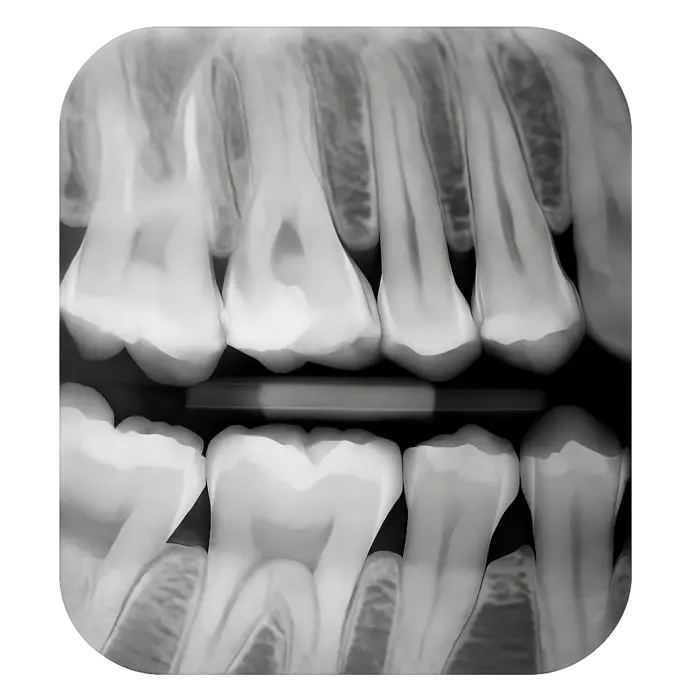

Прикусной рентген-снимок (байтвинговый)

Данный тип снимка фокусируется на верхних и нижних зубах в месте их смыкания. Этот тип рентгена позволяет увидеть зубы, которые соприкасаются между собой, и кости, поддерживающие зубной ряд.

Что показывает:

- Кариес между зубами, особенно на труднодоступных участках.

- Состояние существующих пломб и реставраций.

- Потерю костной ткани вокруг зубов (важно для ранней диагностики пародонтита).

- Скрытые дефекты, которые невозможно заметить при обычном осмотре.